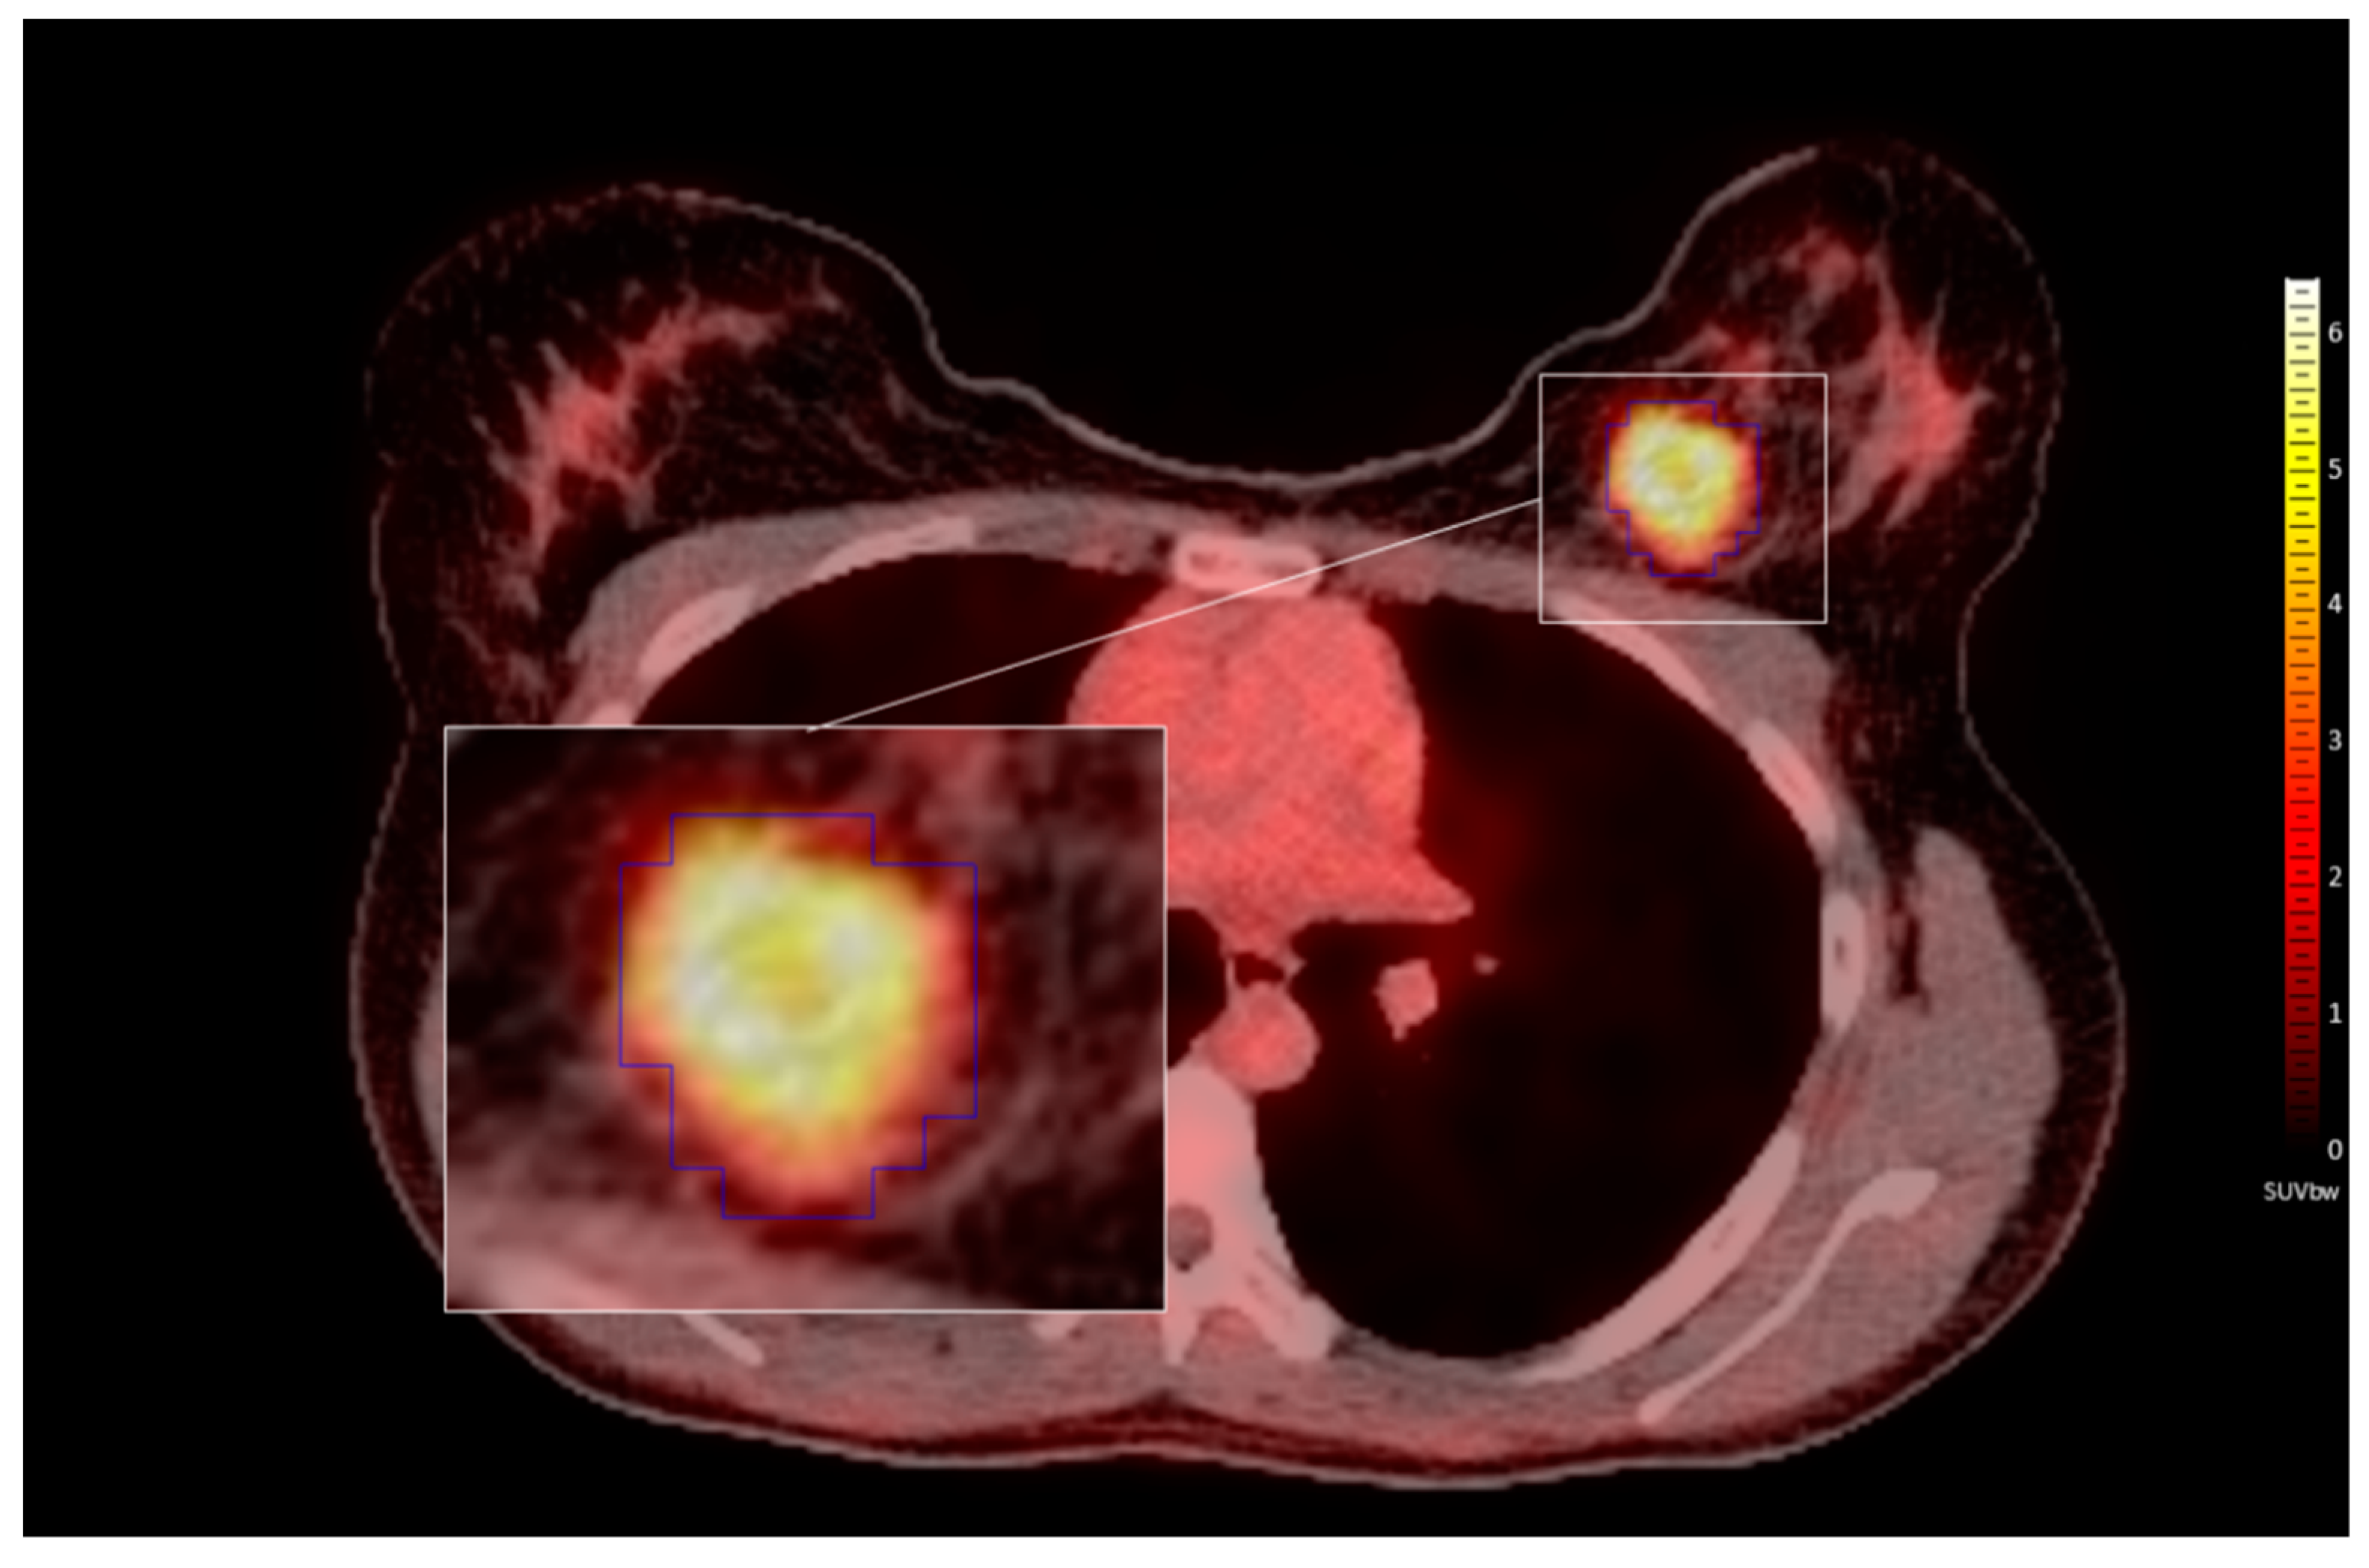

2.3. PET/CT

2.4. Lesion Delineation

2.5. Feature Extraction